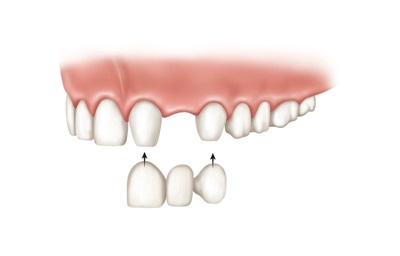

2.固定假牙

好处:不用摘戴,无异物感,较为牢固使用效果好。

缺点:固定假牙需要磨损缺失牙两旁的天然牙来制作固定桥,缺失一颗做“三颗”。且固定桥牙齿是相连的,牙缝难清洁,易藏污纳垢导致蛀牙或牙周病。